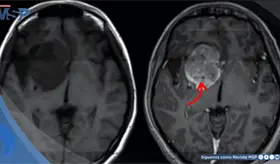

La enfermedad avanzó de forma silenciosa durante años, manifestándose únicamente con cambios de personalidad, deterioro cognitivo e incontinencia, lo que llevó a un diagnóstico tardío.